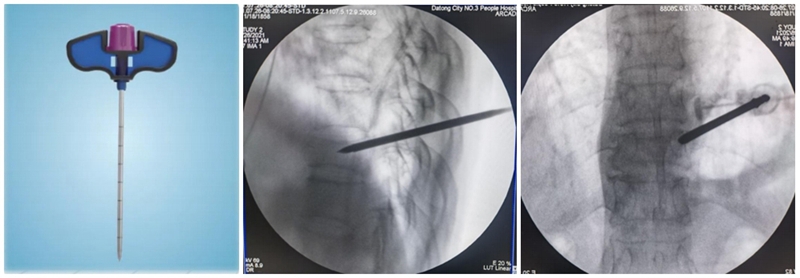

PCKP的优势在于术中操作安全、便捷、骨水泥弥散好,渗漏率低。术中穿刺过程中穿刺针以更小的穿刺角度进入椎体内,通过弯角骨钻开腔越过椎体中线,增加了穿刺安全区间,减少了术中医源性穿刺损伤的风险;同时通过弯角球囊的独特设计,可以在椎体中部造成弧形空腔,引导骨水泥在灌注过程中从穿刺对侧开始弥散,沿球囊撑开的弧形空腔充分灌注,达到单侧穿刺、双侧弥散的效果,有效降低了骨水泥渗漏风险。

(2)弯角导丝开腔:弯角骨钻开腔器械刺入椎体时,注意开腔工具手柄与伤椎终板平行,不要强行开腔,多透视侧位,否则弯导丝可能穿破终板,导致医源性骨水泥渗漏。C形臂X线机正位透视下,导丝到达椎体对侧椎弓根处即可。

(3)弯角骨钻扩张:C形臂X线机正位透视下,弯角骨钻开腔器械螺旋手柄顺时针扭转,让弯角骨钻沿导丝前进开路,将椎体内部钻出弧形通道。操作中注意骨钻沿导丝旋进旋出要完全,旋进不够,后期球囊无法到达对侧,旋出不完全,骨钻会卡在工作套筒上无法拔出。

(4)置入球囊:插入带导丝弯角球囊时注意透视球囊方向,反复调整务必与终板平行。如需要拔出球囊调整方向,务必先拔导丝再拔球囊,透视球囊标记点必须完全从工作套管内出来,否则易造成弯角球囊与工作套管边缘卡磨破裂。

(5)扩张球囊:注入造影剂扩张球囊过程中,注意观察术中正侧位透视图像,控制压力值,不必苛求球囊顶到上下终板,以免发生医源性终板破裂,造成椎间隙骨水泥渗漏可能。注意弯角球囊扩张完毕后拔除顺序:先拔导丝再拔球囊。